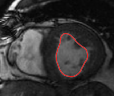

Figures 8 and 9 shows some sample tracking results of the proposed method and Medviso on full cardiac cycles of two different cases on both the LV dataset and the RV dataset. The ground truth (yellow) is superimposed when available. A summary of the results on the entire datasets is shown in Table I. The accuracy with respect to ground truth is measured using average perpendicular distance (APD) and dice metric (DM) for left ventricle, and Hausdorff distance (HD) and DM for the right ventricle. These metrics are chosen since they are the standard ones used on these datasets. Both qualitative and quantitative results show that our proposed method leads to more accurate segmentation of the ventricles and thus leads to less interaction than segmentation propagation schemes in than Medviso.

| initial | ventricle tracked (red - algorithm result, yellow - ground truth) | |||

|---|---|---|---|---|

|

Medviso

![]() |

our method